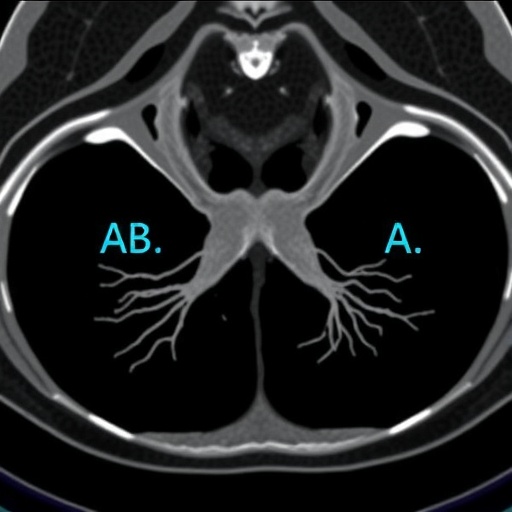

Computed tomography angiography has become increasingly notable for its ability to produce detailed images of blood vessels, offering insights into potential blockages or abnormalities. Unlike traditional invasive procedures, CTA is non-invasive and utilizes modern imaging techniques that allow for rapid assessment of carotid artery health. This immediacy is crucial in emergency settings where every moment counts, particularly in TIA cases. Subsequently, using CTA in conjunction with the ABCD2 score enhances the ability to assess patient risk more effectively.

The ABCD2 score, developed to predict the risk of stroke in patients presenting with TIAs, evaluates five clinical factors: age, blood pressure, clinical features, duration of symptoms, and diabetes status. Each component of the score contributes to an overall assessment that helps stratify patients based on their risk. However, while effective, the ABCD2 score alone has limitations and cannot always differentiate between the severity of risk that various patients may present. By integrating CTA, clinicians can obtain visual confirmation of vascular health, bolstering the predictive power of the ABCD2 score.

In analyzing the study’s findings, it’s evident that this combined approach results in significantly improved diagnostic accuracy. With detailed imaging data from CTA augmenting the predictive models provided by ABCD2, clinicians can make more informed decisions regarding patient management. This could lead to quicker interventions aimed at preventing full-blown strokes, potentially saving lives and improving long-term outcomes.